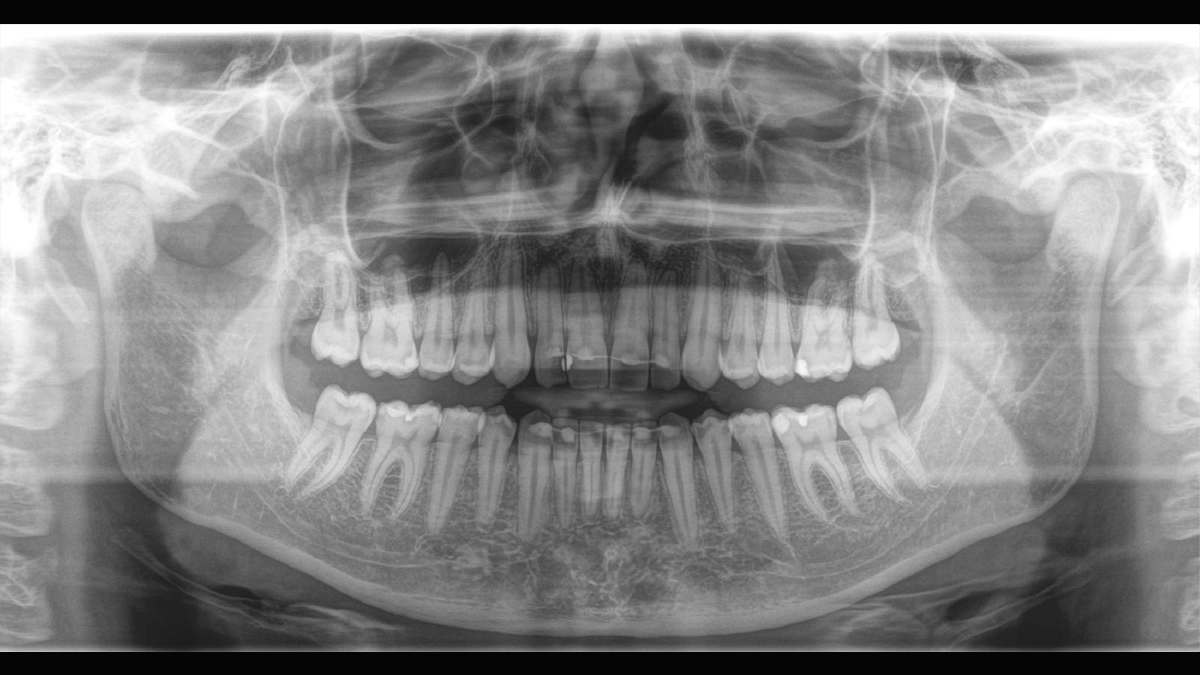

Aunque las radiografías 3D son cada vez más demandadas y existen un gran un número creciente de equipos en consultorios dentales, la imagen 2D sigue teniendo su lugar, en gran medida, debido a su radiación. Las mejoras realizadas en la calidad de imagen hace que las opciones disponibles en tecnología 2D están lejos de haberse agotado. Orthophos SL ha revolucionado la imagen 2D con la introducción del Sensor de Conversión Directa, la tecnología Sharp Layer y la SL interactiva. Experimente imágenes panorámicas como nunca antes.

Galería de muestra de imágenes panorámicas 2D